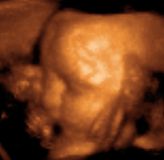

Плод в утробе матери.

Трехмерное ультразвуковое исследование 29-ти недельного плода.